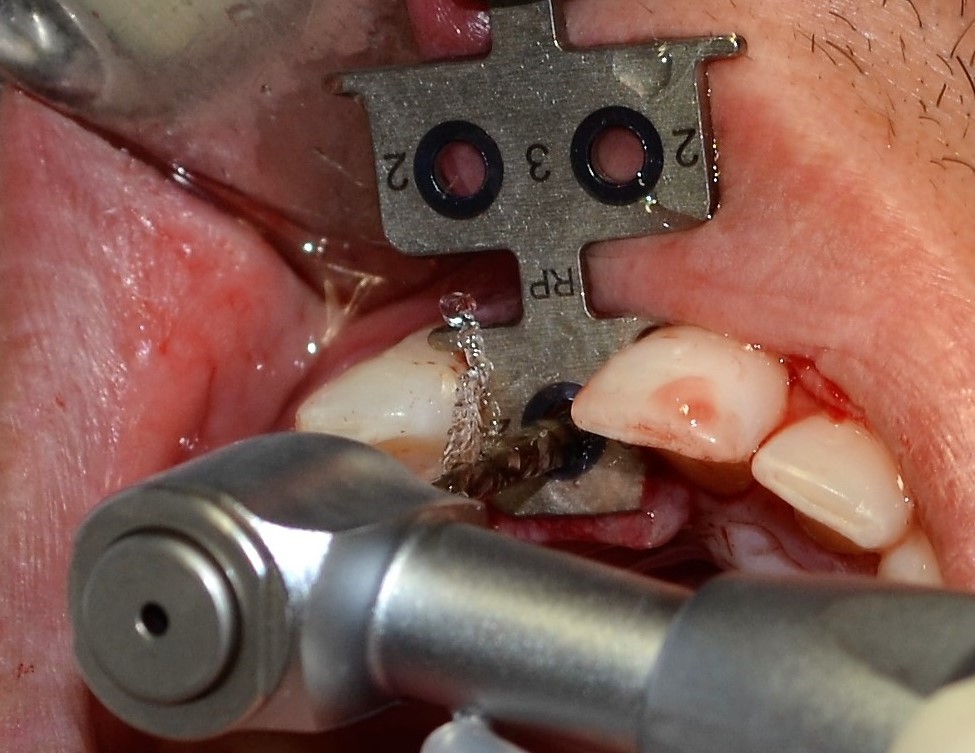

Região do elemento 11 edêntula. Foi realizado o planejamento para instalação de um implante na região desdentada, tentando deixar o mais parecido com o dente vizinho. Após exames complementares e planejamento, foi realizada a instalação de um implante Cone Morse 3.5×10 mm com enxerto Lumina Bone na região vestibular.

Após isso, foi realizado o preenchimento do enxerto com membrana de LPRF. Como o torque adquirido na instalação do implante foi de 25 N, não foi realizado provisionalização imediata.